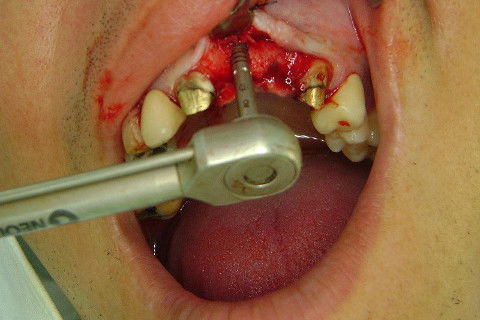

Cirurgia realizada hoje de manhã...No planejamento percebi medindo espessura do rebordo com especímetro que as medidas não estavam muito boas, ou o ideal, em torno de 4,5 a 5 mm ate´o terço médio do rebordo e melhorava no final, com 6 a 7 mm. Optei então por uma pequena expansão usando os expansores rosqueáveis. Aconteceu uma pequena fenestração na hora da fixação dos implantes, especialmente na região do 22 que fraturou o início da tábua óssea, mas não me preocupei porque não foi mais do que 2 mm de fratura em direção apical, o implante ficou infraósseo e com boa estabilidade (60 N no 21 e 40 N no 22). Esta fratura tb não deixou osso completamente solto, foi do tipo galho verde, deixei em posição e suturei normalmente. Só não fiz e nem estava planejado carga imediata mesmo, mais pelo motivo da oclusão inadequada do caso.